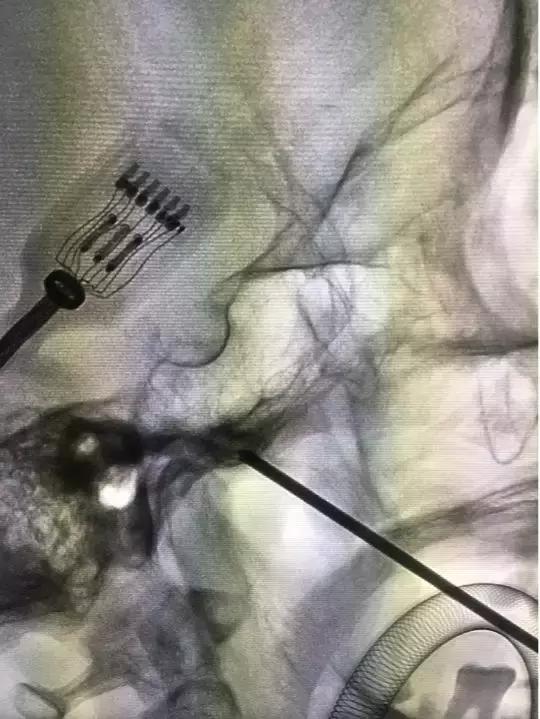

这个手术的核心*器武**就在于一根15厘米长的套管针,手术时要全麻,在神经介入导管室进行,医生从她左嘴角边上2.5厘米的地方将针穿进,通过神经介入DSA设备多角度透视定位,安全引导套管针到达颅内三叉神经根部,然后将针芯抽出,采用神经介入导管操作技术把跟水笔笔头差不多大的球囊通过管道塞到根部,向球囊注射造影剂扩张,持续压迫神经5分钟,使神经发生变化,传导受限,达到治疗效果。

左侧口角外穿刺定位

术中穿刺套管针到位